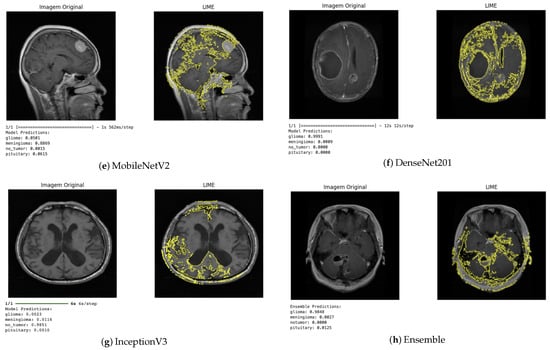

The LIME technique, in turn, provides local explanations by identifying which regions of the image contributed positively or negatively to the classification (Figure 10). This approach enabled a more detailed analysis of the influence of each image segment on the decision-making process. In general, the regions highlighted by LIME showed a high correspondence with those identified by Grad-CAM, reinforcing the consistency of the explanations produced by the different methods.

Figure 10.

LIME visualization for different architectures.

Qualitative analysis of the results obtained using the XAI techniques demonstrated that the models developed not only achieved high quantitative performance but also made decisions based on clinically relevant features. This interpretation is crucial in the medical context, as it provides visual and objective evidence that the models focus on tumor regions rather than irrelevant areas of the image.